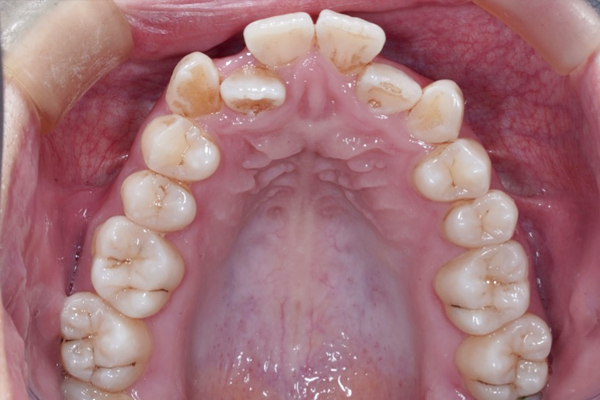

BEFORE

AFTER

• ずっと叢生(ガタガタ)が気になっていた。

• ワイヤー矯正でスペースを作り、非抜歯(抜歯をしないで)並べていく治療方針を計画しました。

• 前歯の重なりが減り、アーチが広がってきました。

【治療方針詳細】

• ワイヤー矯正治療

• 非抜歯矯正治療

• インプラントアンカーにより歯を後ろに動かします。